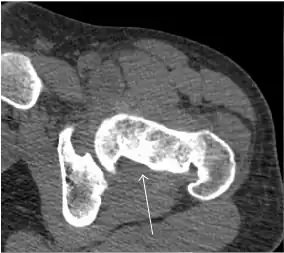

Synovial chondromatosis can be confidently diagnosed by X-ray when calcified cartilaginous chondromas are seen. However, other synovial proliferative processes, such as pigmented villonodular synovitis, require MRI for accurate diagnosis, although noncalcified synovitis can be suspected in radiographs by indirect signs, such as soft tissue swelling and/or erosions in the femoral head, femoral neck, or acetabulum (Figure 7).[1]

Figure 7:

-

Axial CT image of pigmented villonodular synovitis eroding the posterior cortex of the femoral neck.[1] -

In synovial proliferative disorders, MRI demonstrates synovial hypertrophy. In the case of PVNS, characteristic foci of low signal intensity related to hemosiderin deposition are better seen on gradient echo T2* images (Figure 7). In the case of synovial osteochondromatosis, the synovial hypertrophy is accompanied by intermediate signal cartilaginous loose bodies and/or low signal calcified loose bodies.[1]